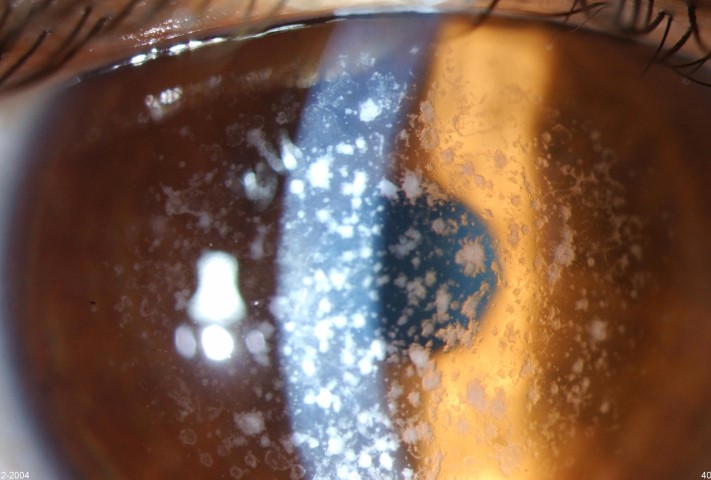

GCD1 is characterised by bilateral deposits in the anterior central stroma appearing as small, discrete, well demarcated, greyish-white opacities, typically appearing during the first or second decade of life. The deposits may first appear as fine dots which later take on a crumb-, ring-, or drop-shaped appearance. These lesions progressively increase in size, number, and may coalesce. Further advancement sees a ground-glass appearance of the cornea develop between lesions. In the early stages, patients normally suffer no discomfort or visual changes, although a subset does suffer erosive episodes. By the fourth decade, visual impairment can begin, typically secondary to opacification of the intervening stroma (Fig 1).

Fig 1b. Confluent breadcrumb granular opacities under direct and retro-illumination